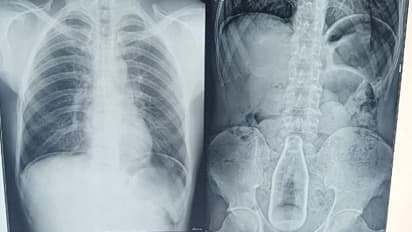

புதுக்கோட்டை மாவட்டத்தைச் சேர்ந்த 45 வயதுடைய ஒரு நபரின் ஆசனவாயில் இருந்து ரத்தம் வந்ததாக கடந்த ஏழு தினங்களுக்கு முன்பாக புதுக்கோட்டை அரசு மருத்துவக் கல்லூரி மருத்துவமனையில் அந்த நபர் அனுமதிக்கப்பட்டார். பிறகு மருத்துவர்கள் அவரது உடலை பரிசோதனை செய்து X-Ray எடுத்து, ஸ்கேன் செய்து பார்த்தபோது மருத்துவர்கள் அதிர்ச்சி அடைந்துள்ளனர். அவரது வயிற்றுக்குள் செவன் அப் பாட்டில் ஒன்று இருந்தது கண்டுபிடிக்கப்பட்டது

உடனடியாக அவரை பரிசோதனை செய்து அவரது உடல் இயல்பு நிலைக்கு வந்த பிறகு கடந்த மூன்று தினங்களுக்கு முன்பாக அவருக்கு அறுவை சிகிச்சை செய்யப்பட்டது. அவருக்கு வயிற்றில் செய்யப்பட்ட அறுவை சிகிச்சை மூலமாக வயிற்றுக்குள் இருந்த அந்த குளிர்பான பாட்டில் எடுக்கப்பட்டது. ஆனால் வயிற்றுக்குள் எப்படி குளிர்பான பாட்டில் சென்றது என்பது குறித்து மருத்துவர்கள் ஆய்வு செய்து வந்தனர்.